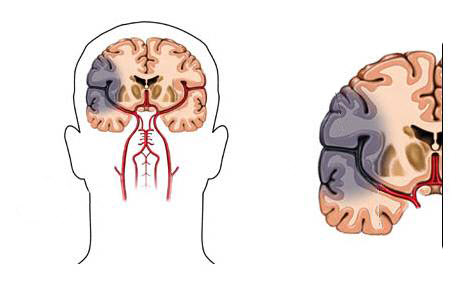

뇌혈관이 막히거나 터지는 질환을 부르는게 뇌졸중이고 그 중 뇌혈관이 막히는게 뇌경색 그리고 뇌혈관이 터지는 것을 뇌출혈이라고 합니다. 뇌졸중은 영구적인 손상이 많다고 하며 증상에 따라 전신이나 육체 일부 기능이 마비되는 등의 극심한 후유증이 남는 무서운 질병입니다 오늘은 뇌경색 초기증상에 대하여 알려드리도록 하겠습니다.

허혈성 뇌졸중은 발생 기전에 따라 대혈관 질환에 의한 뇌경색, 심인성 뇌경색 또는 심인성 뇌경색, 소혈관 질환 또는 틈새 뇌경색, 기타 드문 이유가 되는 것에 의한 뇌경색으로 나누어져요. 에피소드는 일정 기간 동안 증상이 완전히 가라앉는 경우입니다.

허혈성 뇌졸중의 대표적인 이유가 되는 것은 고혈압, 당뇨병, 고지혈증 등으로 인해서 뇌에 혈액을 전달하는 혈관에 동맥경화(동맥경화)가 발생하여 뇌로 가는 혈류를 차단하는 것입니다.